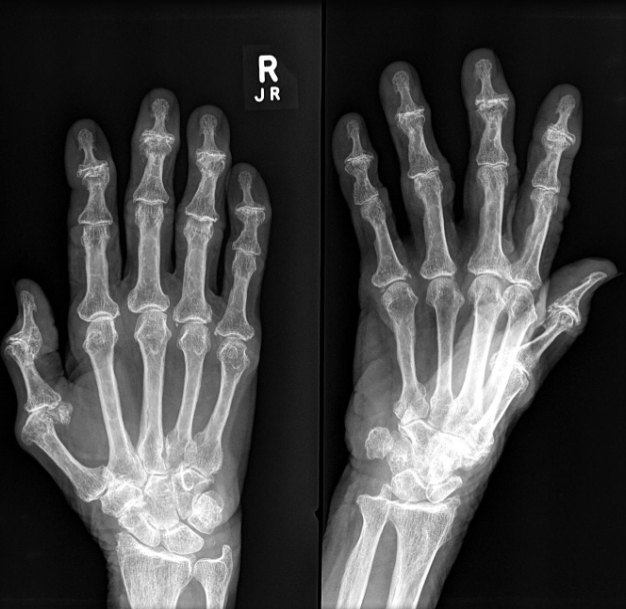

Rheumatoid Arthritis Radiological sign:.

- Around joint, periarticular osteopenia/osteoporosis

- Changes more to the proximal joints than distal

- Swan neck and Boutonnière deformity and extensive erosive